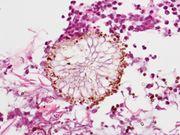

وَرَمُ الرَّشَّاشِيَّات (Aspergilloma): هو عبارة عن هيكل منظم من الكرات الفطرية يتطور في داخل تجويف الرئتين في أعقاب حصول تَنَدُّب في الرئتين بسبب الإصابة بمرض سابق، مثل السل (Tuberculosis) أو الخراجات (Abscess) الرئوية.